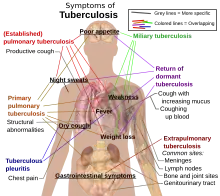

| Symptômes | Toux, hémoptysie, amaigrissement, fièvre, sueurs nocturnes, douleur thoracique, fatigue physiologique (d) et frissonnement (en) |

Clinique

La tuberculose peut revêtir différentes formes selon la localisation du foyer infectieux. La tuberculose pulmonaire est la forme la plus fréquente et la source essentielle de la contagion. À partir du poumon, le bacille peut diffuser dans l'organisme et causer d'autres atteintes, ganglionnaires, ostéoarticulaires et urogénitales notamment. Les formes les plus létales sont les formes diffuses (miliaires) et méningées.

La tuberculose pulmonaire est la forme la plus fréquente et présente plus de 85 % des cas[49],[50]. Le tableau le plus classique et le plus fréquent chez les tuberculeux pulmonaires laisse définir le syndrome d’imprégnation tuberculeuse : fièvre, sueur nocturne, amaigrissement, anorexie[50].

- signes généraux : signes d’imprégnation tuberculeuse, fébricule, sueurs nocturnes et aménorrhée chez la femme ;

- signes fonctionnels apparents au début de l’affection et sont durables à plus de 15 jours. ils sont marqués principalement par les signes suivants : toux productive, expectoration purulente, dyspnée ;

En revanche quand il s’agit d’une installation brutale, l’hémoptysie et crachats sanguins sont plus observés chez les personnes atteintes ainsi que l’épanchement pleural est observé que ce soit aérien ou liquidien[52].